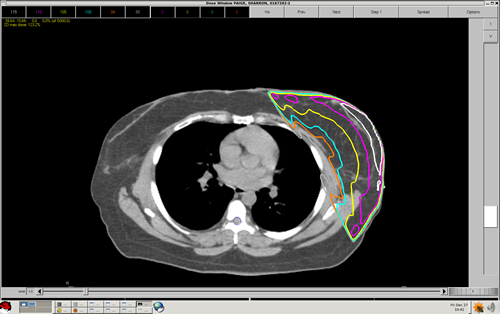

When adding a wedge (or wedges) to a typical breast cancer treatment plan, the orientation of the wedge(s) is: a) Heel to posterior/medial – toward the thickest part of the breast b) Heel anterior/lateral – toward the nipple of the breast c) Heel superior – toward the head of the patient d) Heel inferior – toward the feet of the patient